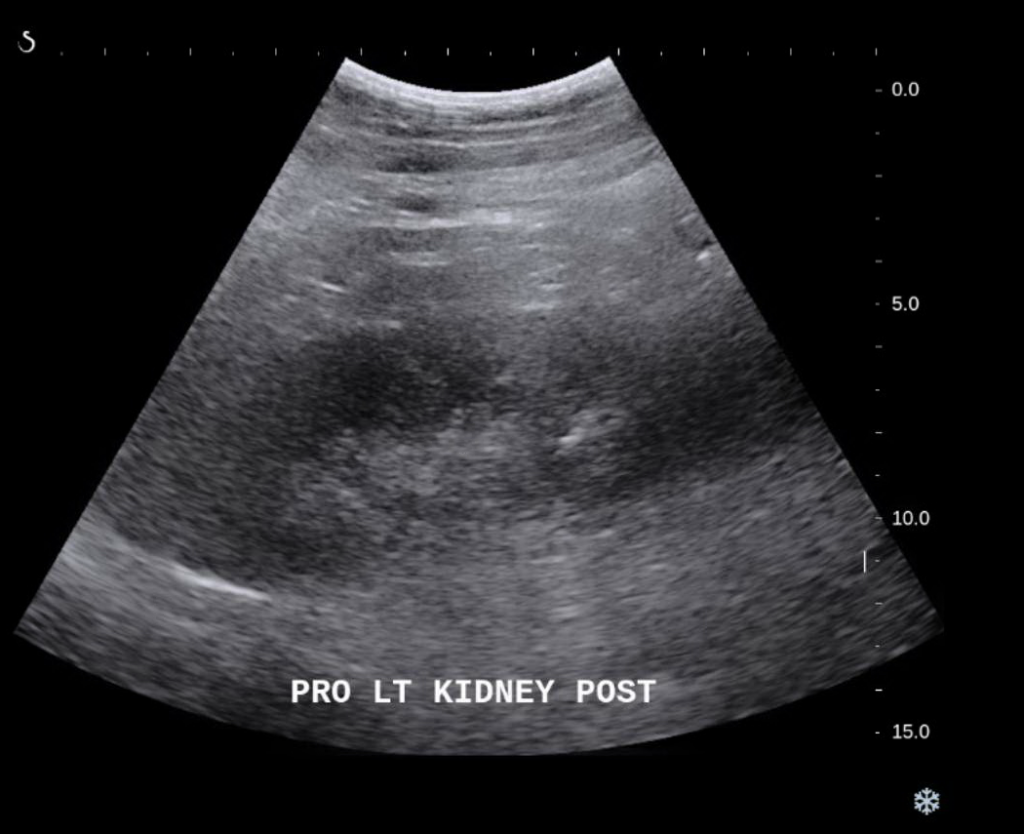

Ultrasound image obtained during percutaneous renal biopsy. Arrow... Download Scientific Diagram Kidney Biopsy Ultrasound Guided This is the most common type of kidney biopsy. During a kidney biopsy, a healthcare professional uses a needle to remove a small sample of kidney tissue for lab testing. A biopsy sample can be done in one of two ways: They’ll numb your skin and insert a needle to take the kidney. A needle is placed through the skin. Kidney Biopsy Ultrasound Guided.